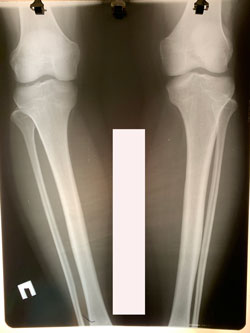

Исходник - 33 года.

Дата операции - 25.01.2021